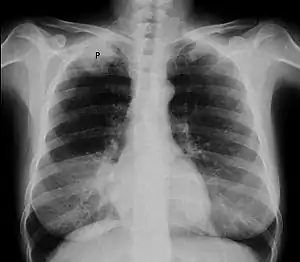

| 胸部X光片,顯示右肺潘科斯特腫瘤(圖上P處);患者為47歲有抽菸史女性,罹患非小細胞肺癌。 | |

通常在评估临床症状與影像學檢查後可诊断之。胸部X光是不錯的初步檢查,但胸部電腦斷層掃瞄可以提供更好的解析度與判斷對內臟的影響。

電腦斷層扫描显示一名47岁女性吸烟者患有潘科斯特肿瘤(标记P處:非小细胞肺癌,右肺)